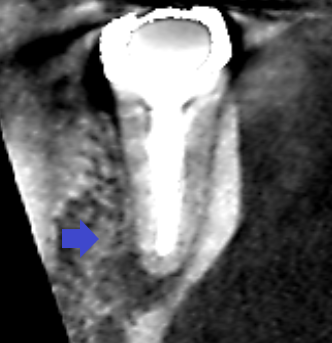

下顎第二大臼歯の矢状断のCT画像です。

矢印の先に膿の影がみられます。根管は、根の先の近くで90°近く曲がっています。再根管治療が難しいケースです。